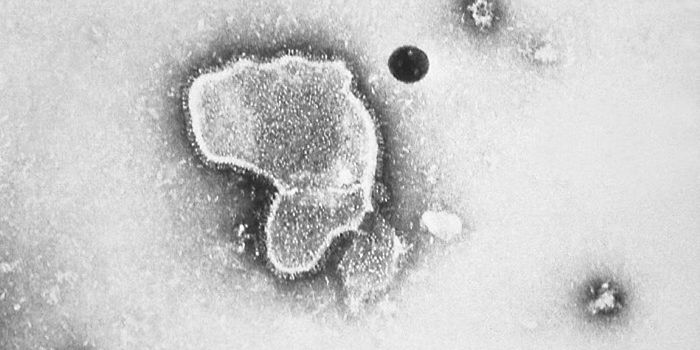

DEC 15, 2018Cell & Molecular BiologyResearchers have been trying to create a vaccine for HIV, the virus that causes AIDS, for decades.

DEC 01, 2014MicrobiologyTimely surveillance warranted to help prevent "the Next Epidemic"

A family of viruses that can be deadly may ... -

MAY 10, 2021MicrobiologyThe pandemic virus SARS-CoV-2 has changed the world in devastating ways, taking hundreds of thousands of lives & new var ...

DEC 09, 2017ImmunologyThe Epstein-Barr virus (EBV) infects almost everyone by the time they’re 30, but not everyone necessarily shows sy ...